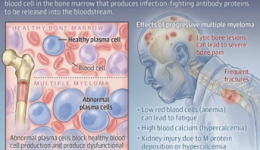

疾病简介:多发性骨髓瘤(MM)是一种克隆浆细胞异常增殖的恶性疾病,是血液系统第2位常见的恶性肿瘤,多发于老年,目前为止仍是不可治愈的血液系统恶性肿瘤,大多数MM患者可能会经历多次复发,而每一次复发后患者产生的耐药性较之前更强,尤其是三...

多发性骨髓瘤周围神经病变的新型血清标志物及经方干预该病的可能机制探讨1多发性骨髓瘤周围神经病变简介多发性骨髓瘤(Multiplemyeloma,MM)是第二常见的血液系统恶性肿瘤,其特征是骨髓中异常浆细胞的克隆性扩增。浆细胞恶性增殖的同时分泌产生大...

一、认识多发性骨髓瘤髓外病变(Extramedullarydisease,EMD):多发性骨髓瘤髓外病变(EMD)的定义为浆细胞肿瘤浸润至骨骼以外的组织(如淋巴结、肝脏、脾脏、软组织等),部分研究也将骨旁浆细胞瘤也纳入EMD范畴。临床数据显示,EMD在初诊MM患者...

一、认识多发性骨髓瘤髓外病变(Extramedullarydisease,EMD):多发性骨髓瘤髓外病变(EMD)的定义为浆细胞肿瘤浸润至骨骼以外的组织(如淋巴结、肝脏、脾脏、软组织等),部分研究也将骨旁浆细胞瘤也纳入EMD范畴。临床数据显示,EMD在初诊MM患者...